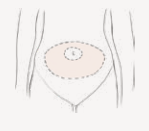

De embryotransfer vindt plaats onder echoscopisch zicht via de buik. Dit betekent dat de plaatsing met de echo via de buik gevolgd wordt om zo nauwkeurig mogelijk de juiste plaats in de baarmoeder te bepalen. Om het goed te kunnen zien, is een gevulde blaas noodzakelijk (zie 1e tekening).

Figuur 8. Volle blaas voor embryotransfer.